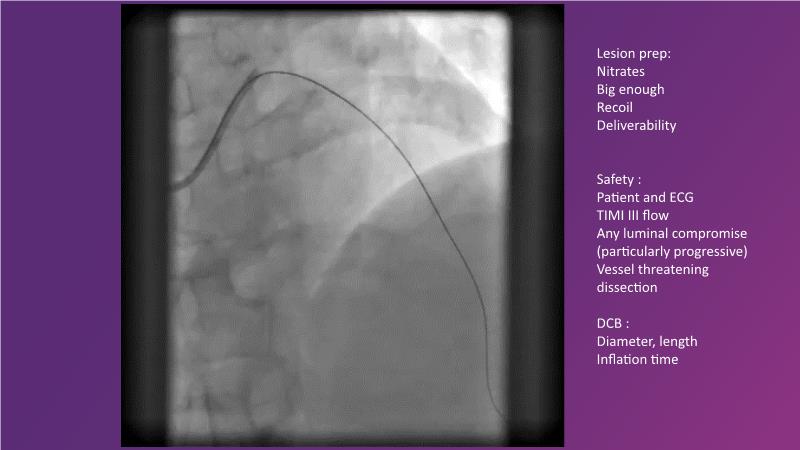

DES and DCB, can these two technologies be complementary for the treatment of the same patient? What are the advantages and how to proceed? You will know everything by watching this presentation based on concrete cases.